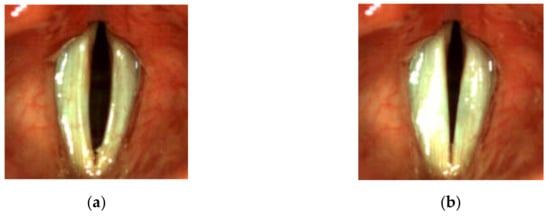

For all subjects, after a routine Ear, Nose, and Throat (ENT) examination, the imaging recordings of the larynx were performed using an LHSV system. In the normophonic patients, the LHSV examination showed no significant deviations in the regularity and symmetry of vocal folds vibrations, mucosal wave, and glottal closure (Figure 1).

Figure 1. Images of the glottis for the normophonic subject N3 for the maximum opening (a) and maximum closing (b) of the vocal folds correspondingly.